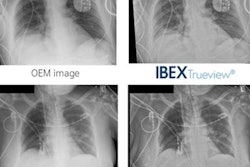

The AI software was developed using machine learning and trained on hundreds of thousands of image samples, Ibex Medical Analytics said. The software is already in use at the pathology institute of Maccabi Healthcare Services, Israel's second-largest HMO, where it is used as a second-read.